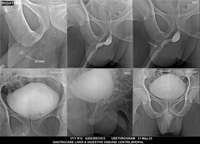

Section: URETHROGRAM Total: 95 images